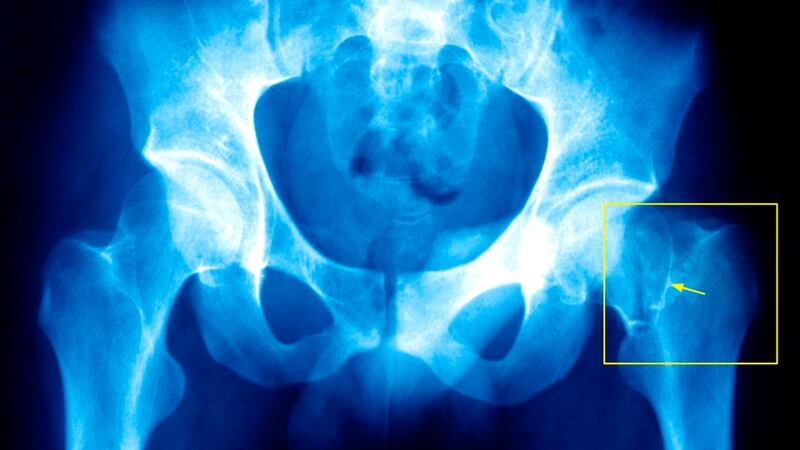

That led to a PhD on the biomechanical properties of bone in osteoporosis, where bones can become fragile and susceptible to fracture. Then O’Brien moved to Boston on a Fulbright scholarship to work at Harvard and MIT in the area of tissue engineering, which seeks to encourage repair in the body after damage.